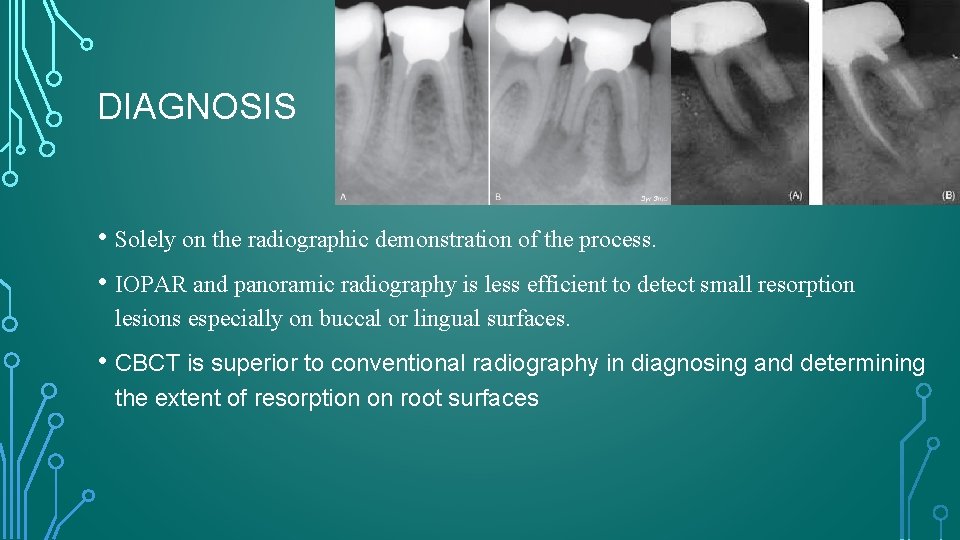

DIAGNOSIS • Solely on the radiographic demonstration of the process. • IOPAR and panoramic radiography is less efficient to detect small resorption lesions especially on buccal or lingual surfaces. • CBCT is superior to conventional radiography in diagnosing and determining the extent of resorption on root surfaces

Andersen et al. and Goldberg et al. concluded that “radiology is not a very accurate procedure for achieving an early and precise diagnosis of resorption defects. ” This study further reported that lesions created on the proximal root surfaces were easier to detect than those on the buccal/lingual surfaces and that the best results were achieved when multiple angled views and preoperative radiographs were available. A more recent study by the King’s College London (KCL) group concluded that CBCT was a reliable and valid method of detecting simulated EIR, and performed significantly better than intraoral periapical radiography.